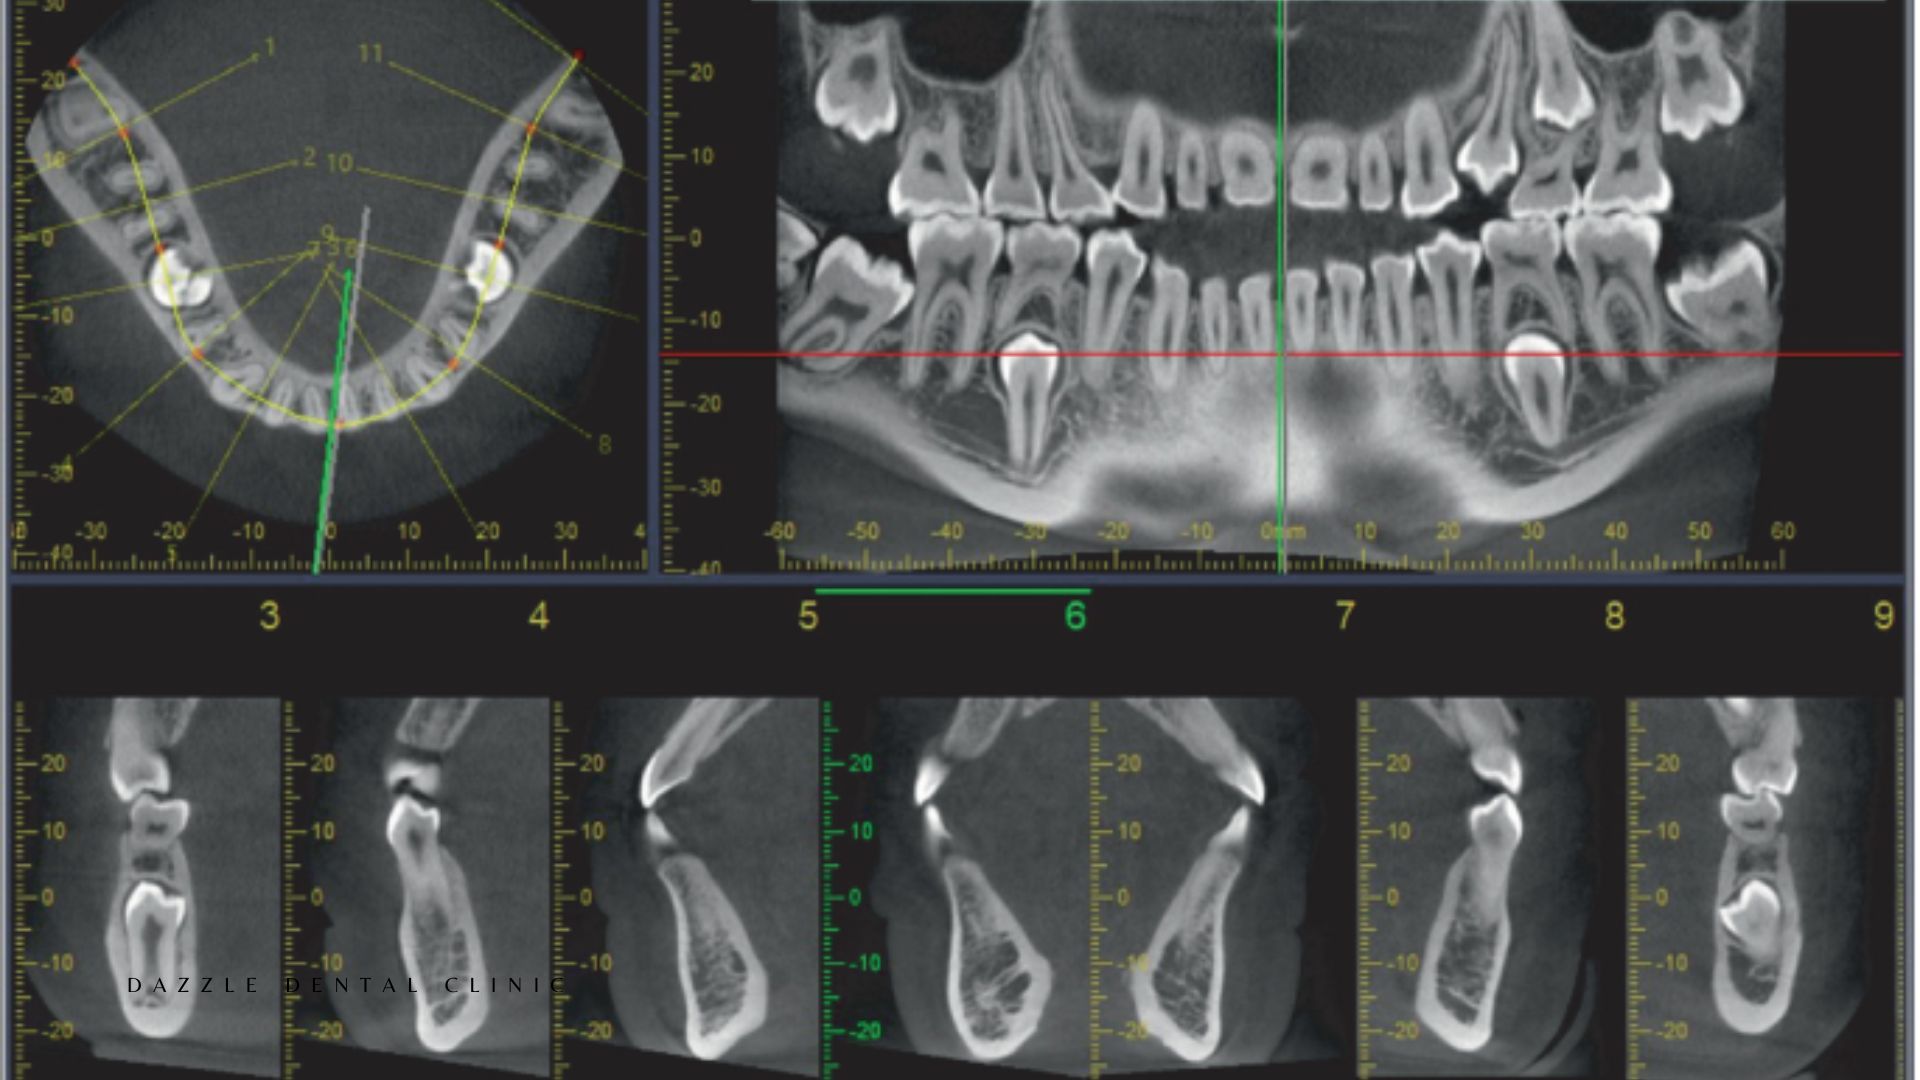

Radiographic monitoring — periapical X-rays around each implant — annually in the first two years, then every two to three years if stable. Marginal bone levels are measured to detect early resorption before it becomes clinically significant.